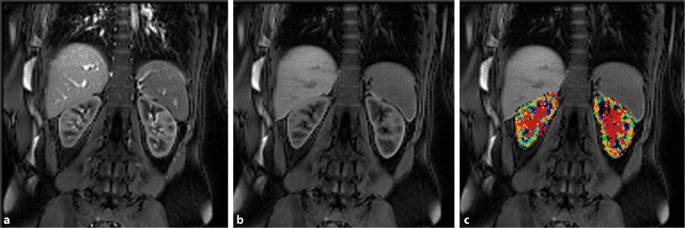

Mri Scan In Tumkur : It produces pictures from angles all around the body and shows up soft tissues very clearly.